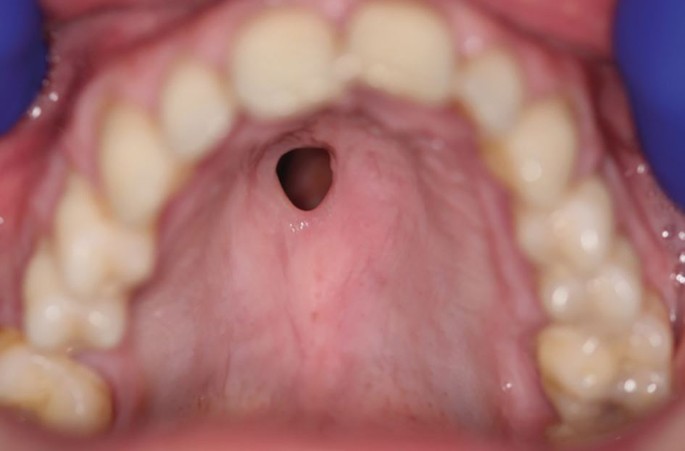

On examination, the patient had a visible lack of nasal columella but no saddle nose deformity (Fig. 1). Intra-orally, there was a fenestration of the left hard palate with direct communication with the nasal cavity. There was an absence of erythema or crusting surrounding the defect (Fig. 2, Fig. 3).

CIMDL with extensive oral and nasopharyngeal destruction